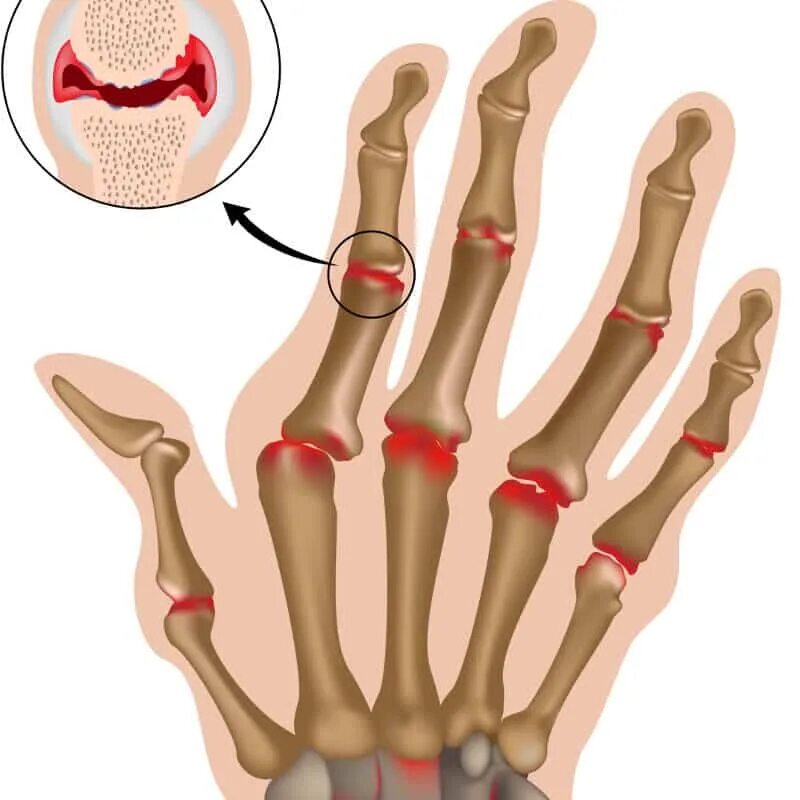

Ревматизм ног